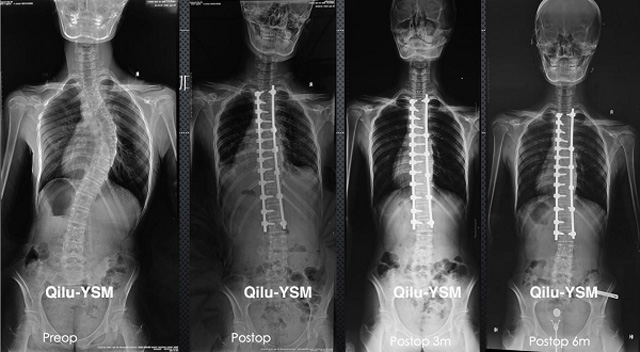

懸吊DR-全電動型機架DR檢查主要用于胸部、四肢、關節(jié)、脊柱等,主要檢查肺部炎癥、腫瘤、結核病、四肢骨關節(jié)的骨折、四肢關節(jié)、脊柱外傷等。DR就是X光,是一種數碼影像,曝光時間很短,攝像量很小,影像質量也很好,可以說是一種替代CR的方法。DR檢查有其局限性,需要做CT平掃等檢查,周圍淋巴結的轉移以確定病變的良惡性、范圍、大小、與鄰近組織的關系。